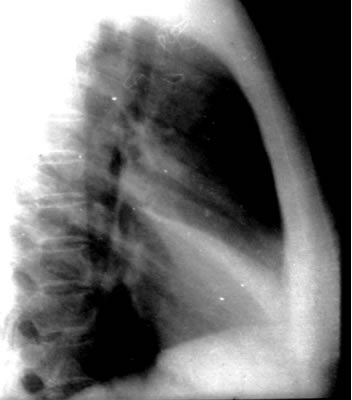

右中叶肺不张(图)

(侧位)右中叶肺不张